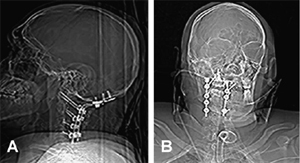

Fig. 3. (A) Lateral and (B) anteroposterior postoperative radiograph demonstrating fixation from the occiput to C4.

entry through an incision spanning the external occipital protuberance to C5. The right posterior arch and lateral mass of C1, right C2 lamina and spinous process, and right C3 superior lamina were removed. The right C2 nerve root was also sacrificed. A stabilisation procedure from the occiput to C4 was performed using onlay bone graft from the iliac crest for posterolateral bone fusion, with instrumentation consisting of an occipital plate, C1 lateral mass fixation and C2–C4 lateral mass screws (Fig. 3). Haemostatic material was required anterior to the cord at C2/3. Time taken was 11 hours.